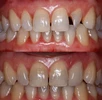

Zirkonyum uygulamalar

Porselen uygulamaları

Laminate veneer